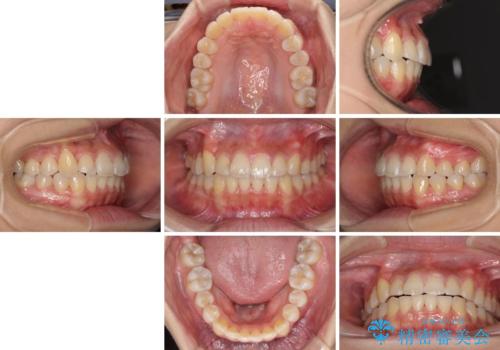

- 前歯のでこぼこと乳歯が残るほどの八重歯を気にして来院された患者様です。

非抜歯にてワイヤー矯正にて治療することとしました。(ただし、親知らずと乳歯は抜歯)

犬歯は歯根が太く長いため、移動には時間を要します。しかし、犬歯は機能面から考えて残すことを選択したいため、長期間をかけて治療を行うこととしました。

治療の度に歯列が改善していったため、長期間の治療も楽しく過ごしていいただき、満足のいく仕上がりとなりました。